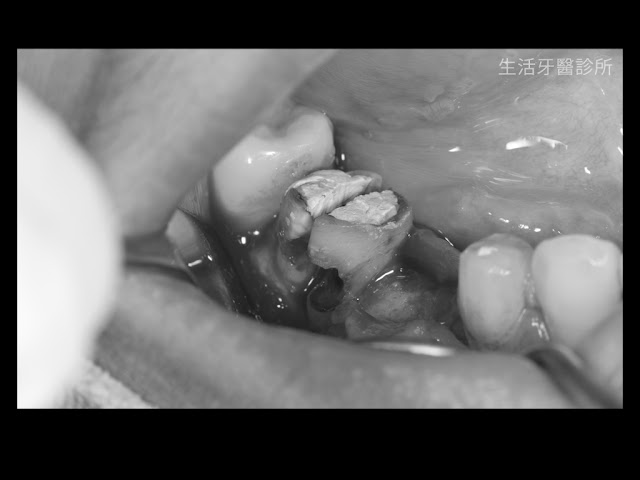

經歷了修磨牙齒、取模後,牙技師送回了漂亮完美的陶瓷貼片成品

接下來在防水隔布的隔濕下,完成美白陶瓷貼片的黏著